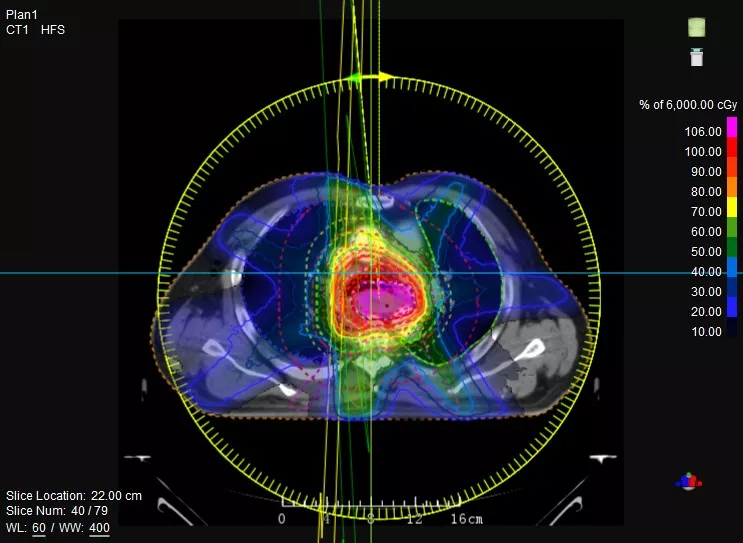

一款設(shè)備即可滿足CT模擬定位、CT影像引導(dǎo)、uARC動態(tài)旋轉(zhuǎn)調(diào)強放療等重要臨床應(yīng)用,無需科室/治療室間切換,一站完成放療全流程。

機(jī)載CT影像可直接用于放療計劃制作

CT-IGRT配準(zhǔn),除骨性標(biāo)記外,還能以器官、軟組織等作為參考,真正找到配準(zhǔn)目標(biāo)